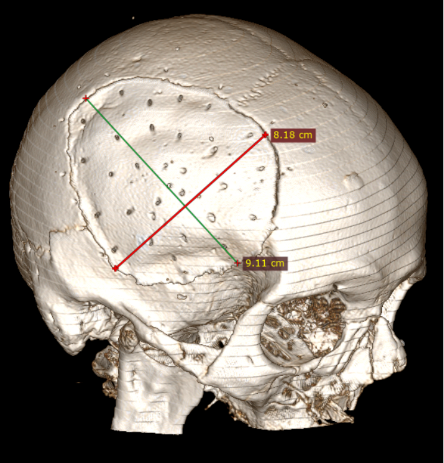

6 pav. Perforacijos KPL

Po pusės metų vyras konsultuotas ambulatoriškai planine tvarka. Atlikus GKT, nustatyta nedidelė lėtinė SDH dešinėje pusėje parietaliai. Po mėnesio suplanuota atlikti KP. Operacijos metu suformuotas kranioplastikos lopas (KPL) iš kraniocemento. Atlikta daugybinių KPL perforacijų (6 pav.), KPL fiksuotas prie kaukolės 10 siūlių. Kitą dieną po operacijos atlikta kontrolinė GKT (7 pav.): po KPL nustatyta hemostatinė medžiaga ir ~20 mm storio ūminė epidurinė hematoma. Vidurio struktūrų dislokacija į kairę – iki 3 mm. Dešinėje pusėje, poodyje – pooperacinė sankaupa su pakraujavimu. Tą pačią dieną atlikta skubi operacija epidurinei ir periostinei hematomoms pašalinti. Aktyvaus kraujavimo operacijos metu nenustatyta. KPL grąžintas, minkštieji audiniai susiūti (8 pav.). Po operacijos paciento būklė buvo stabili, patologinių neurologinių simptomų nenustatyta. Praėjus 2 savaitėms, esant sklandžiai pooperacinei eigai, vyras perkeltas į slaugos ligoninę.

Straipsnyje aptariamu atveju paciento KPL skirtinas mažiausiai (75 cm2) grupei, kuriai būdinga minimali infekcijos atsiradimo rizika (13 pav.), tačiau operacijos metu vis tiek buvo paimtas mikrobiologinis pasėlis infekcijai ekskliuduoti. Mokslinėje literatūroje taip pat pristatomas siekis tirti skirtingų pirminių galvos smegenų hematomų, po kurių reikėjo atlikti kraniektomiją, koreliaciją su EDS, tačiau reikšmingų rezultatų negauta [8].

13 pav. Kranioplastikos lopo dydis (iki 75 cm2)